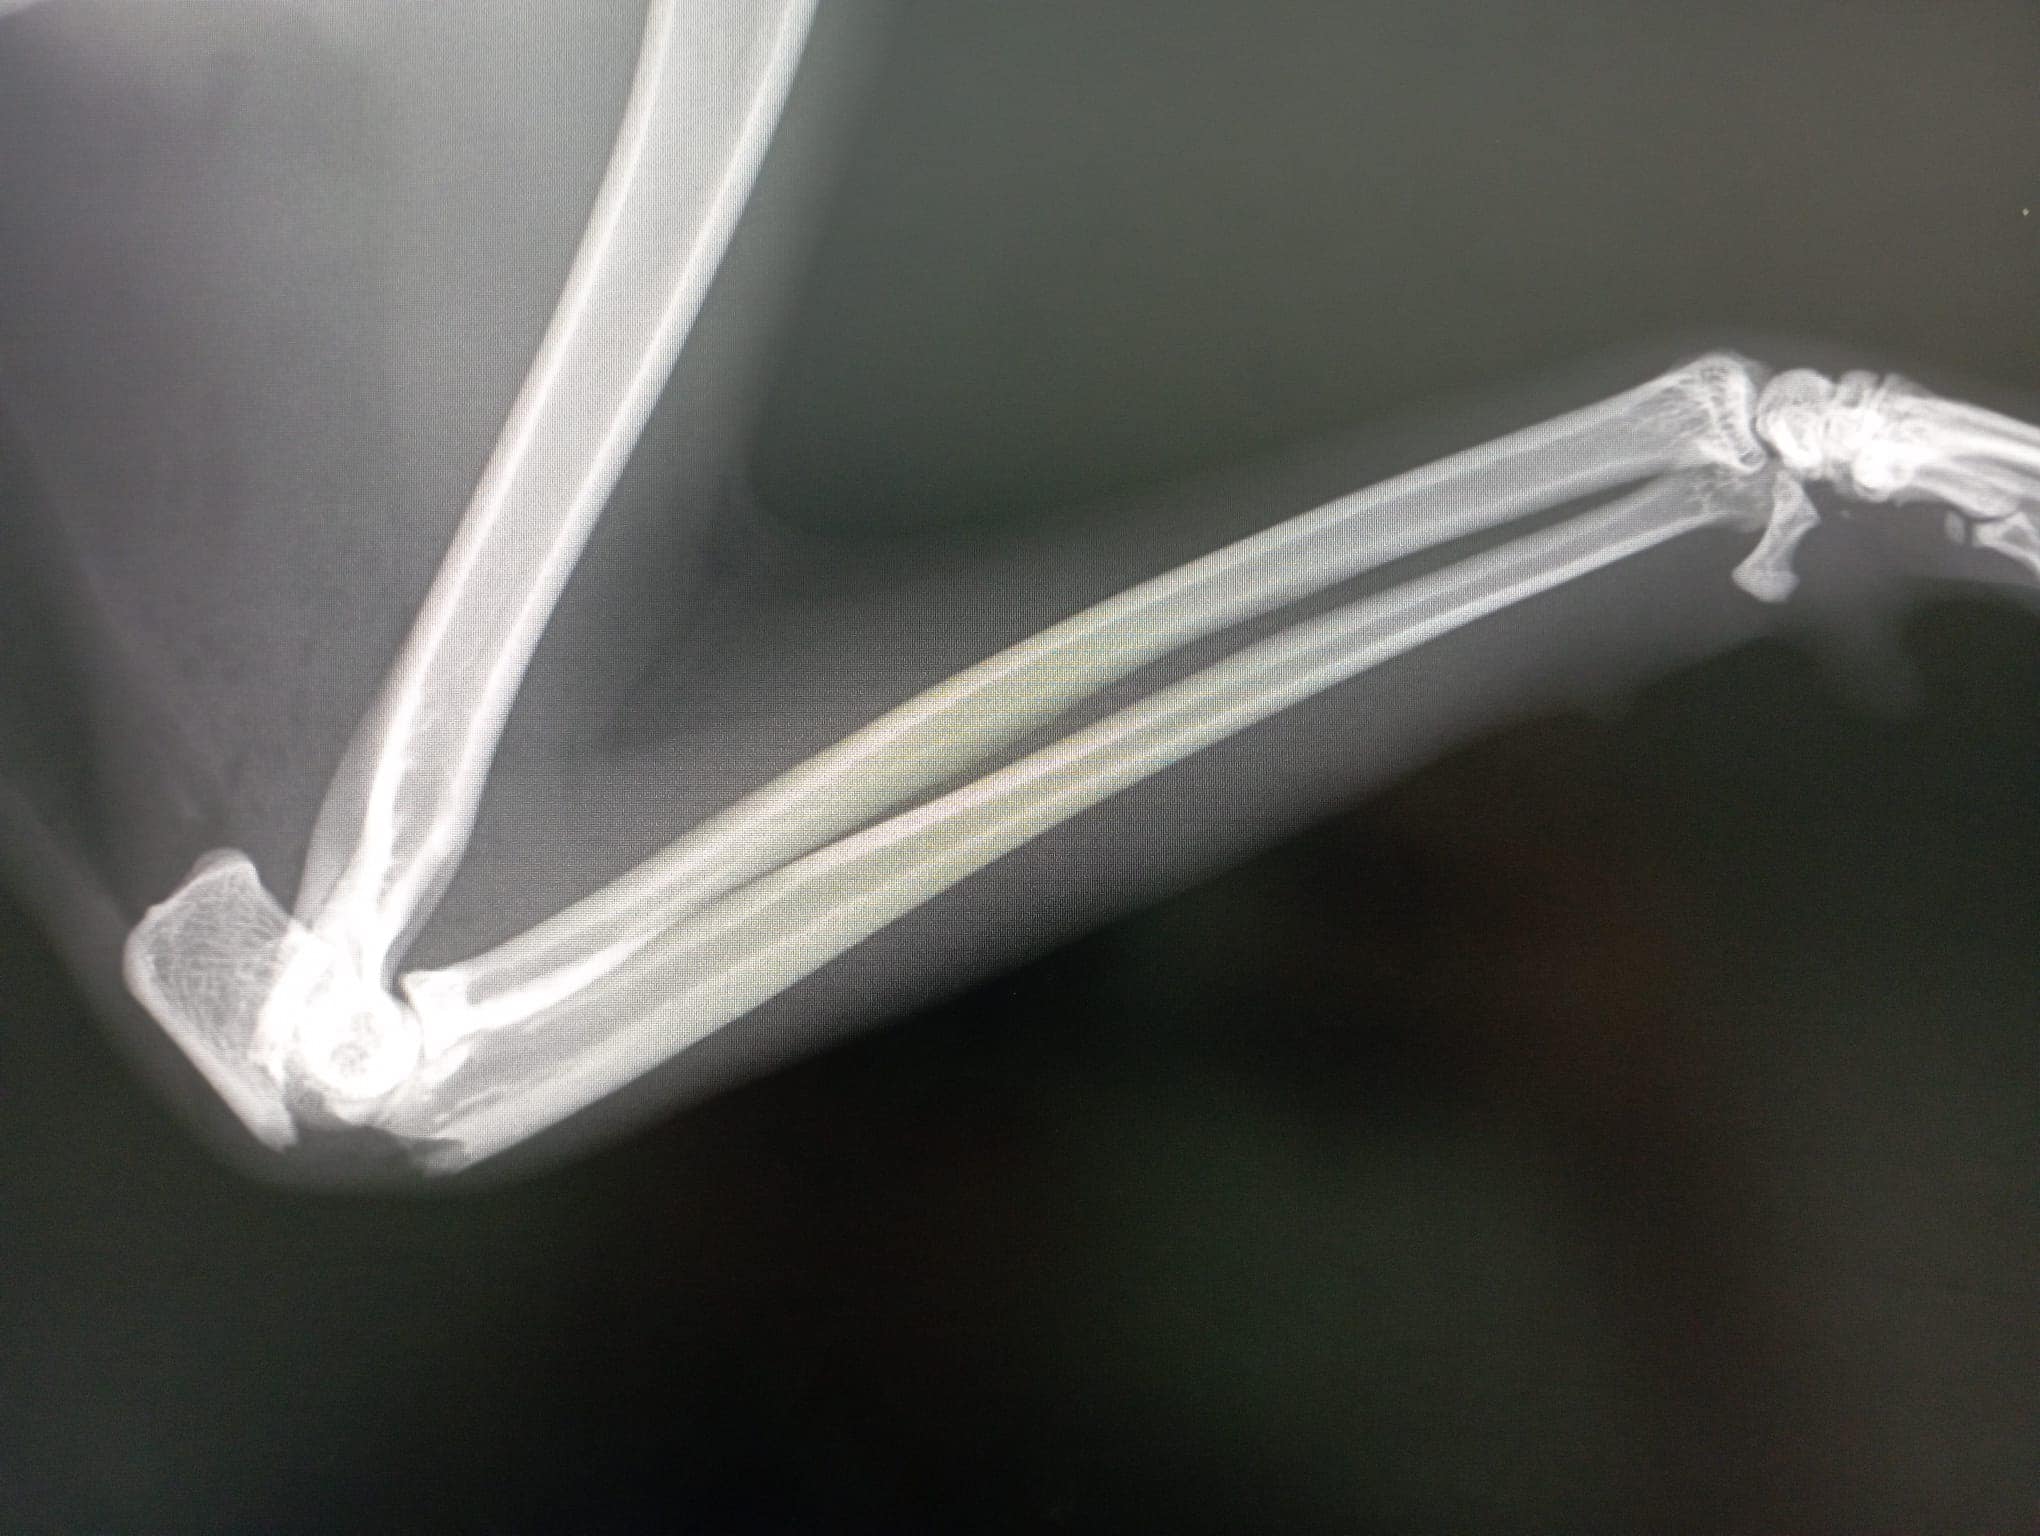

Fratura do olécrano (cotovelo esquerdo) , resultante de um atropelamento recente.

Fratura do íleo (anca direita) , com cerca de 2 a 3 semanas, indicando um segundo atropelamento.

Possível lesão no carpo direito , que pode exigir uma panartrodese no futuro.